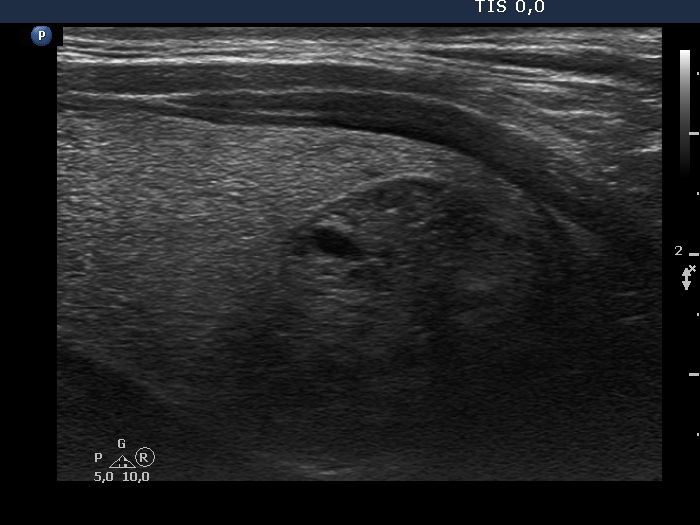

Intranodular hyperechogenic figures - case 975 (ultrasonographic picture 6)

Lower part of the right lobe, longitudinal scan.